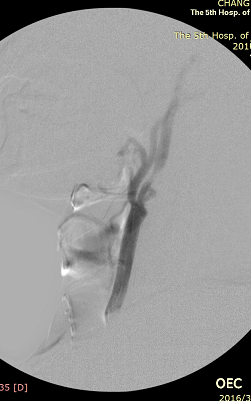

手术如期进行,正如术前所料,右颈动脉斑块的性质不佳,手术难度、风险极大,但王兵副院长带领崔文军副主任医师和安乾、司江涛主治医师克服了重重困难,有惊无险地顺利完成手术,成功地在凹凸不平的血管内、斑块上置入了一枚支架,解除了狭窄、改善了血流、阻隔了斑块,达到了非常满意的效果。术后患者头晕症状很快消失,1周后顺利出院,恢复了正常的生活。

术中支架置入前造影